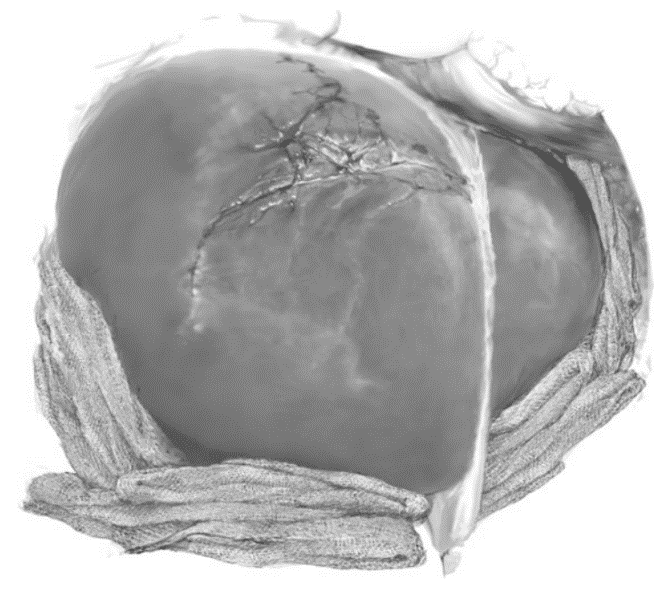

Trong các trường hợp vỡ gan phức tạp, chèn gạc quanh gan (Hình 4) được áp dụng nhằm hạn chế tỷ lệ tử vong do cắt gan lớn gây ra (>50%). Mục tiêu là sớm xử trí tổn thương, cầm máu với việc giảm tối thiểu rủi ro tiến triển đến bộ ba gây chết người (hạ huyết áp, nhiễm toan và rối loạn đông máu). Điều này có hiệu quả đối với nhiều trường hợp chấn thương gan ngoại trừ chấn thương rách các tĩnh mạch sau gan. Chấn thương phức tạp các tĩnh mạch sau gan/tĩnh mạch chủ dưới thường gây tử vong [14].

Chèn gạc được chỉ định khi: (1) Thiếu máu truyền, thiếu phương tiện, khả năng kỹ thuật, thiếu kinh nghiệm trong phẫu thuật chấn thương gan; (2) Chảy máu tiếp diễn dù đã áp dụng các biện pháp cầm máu khác; (3) Tổn thương nặng, phức tạp cả hai thùy gan; (4) Có rối loạn đông máu hoặc có các dấu hiệu xấu như hạ thân nhiệt <35oC, toan chuyển hóa pH <7.3; (5) Cần kết thúc nhanh phẫu thuật do hạ thân nhiệt sâu kèm theo tình trạng tim mạch, huyết động không ổn định.

Hình 4. Chèn gạc cầm máu trong chấn thương gan